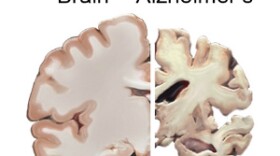

Doctors at Rochester Regional Health and the University of Rochester Medical Center say side effects of some of the drugs that older patients take can combine to resemble symptoms of dementia.